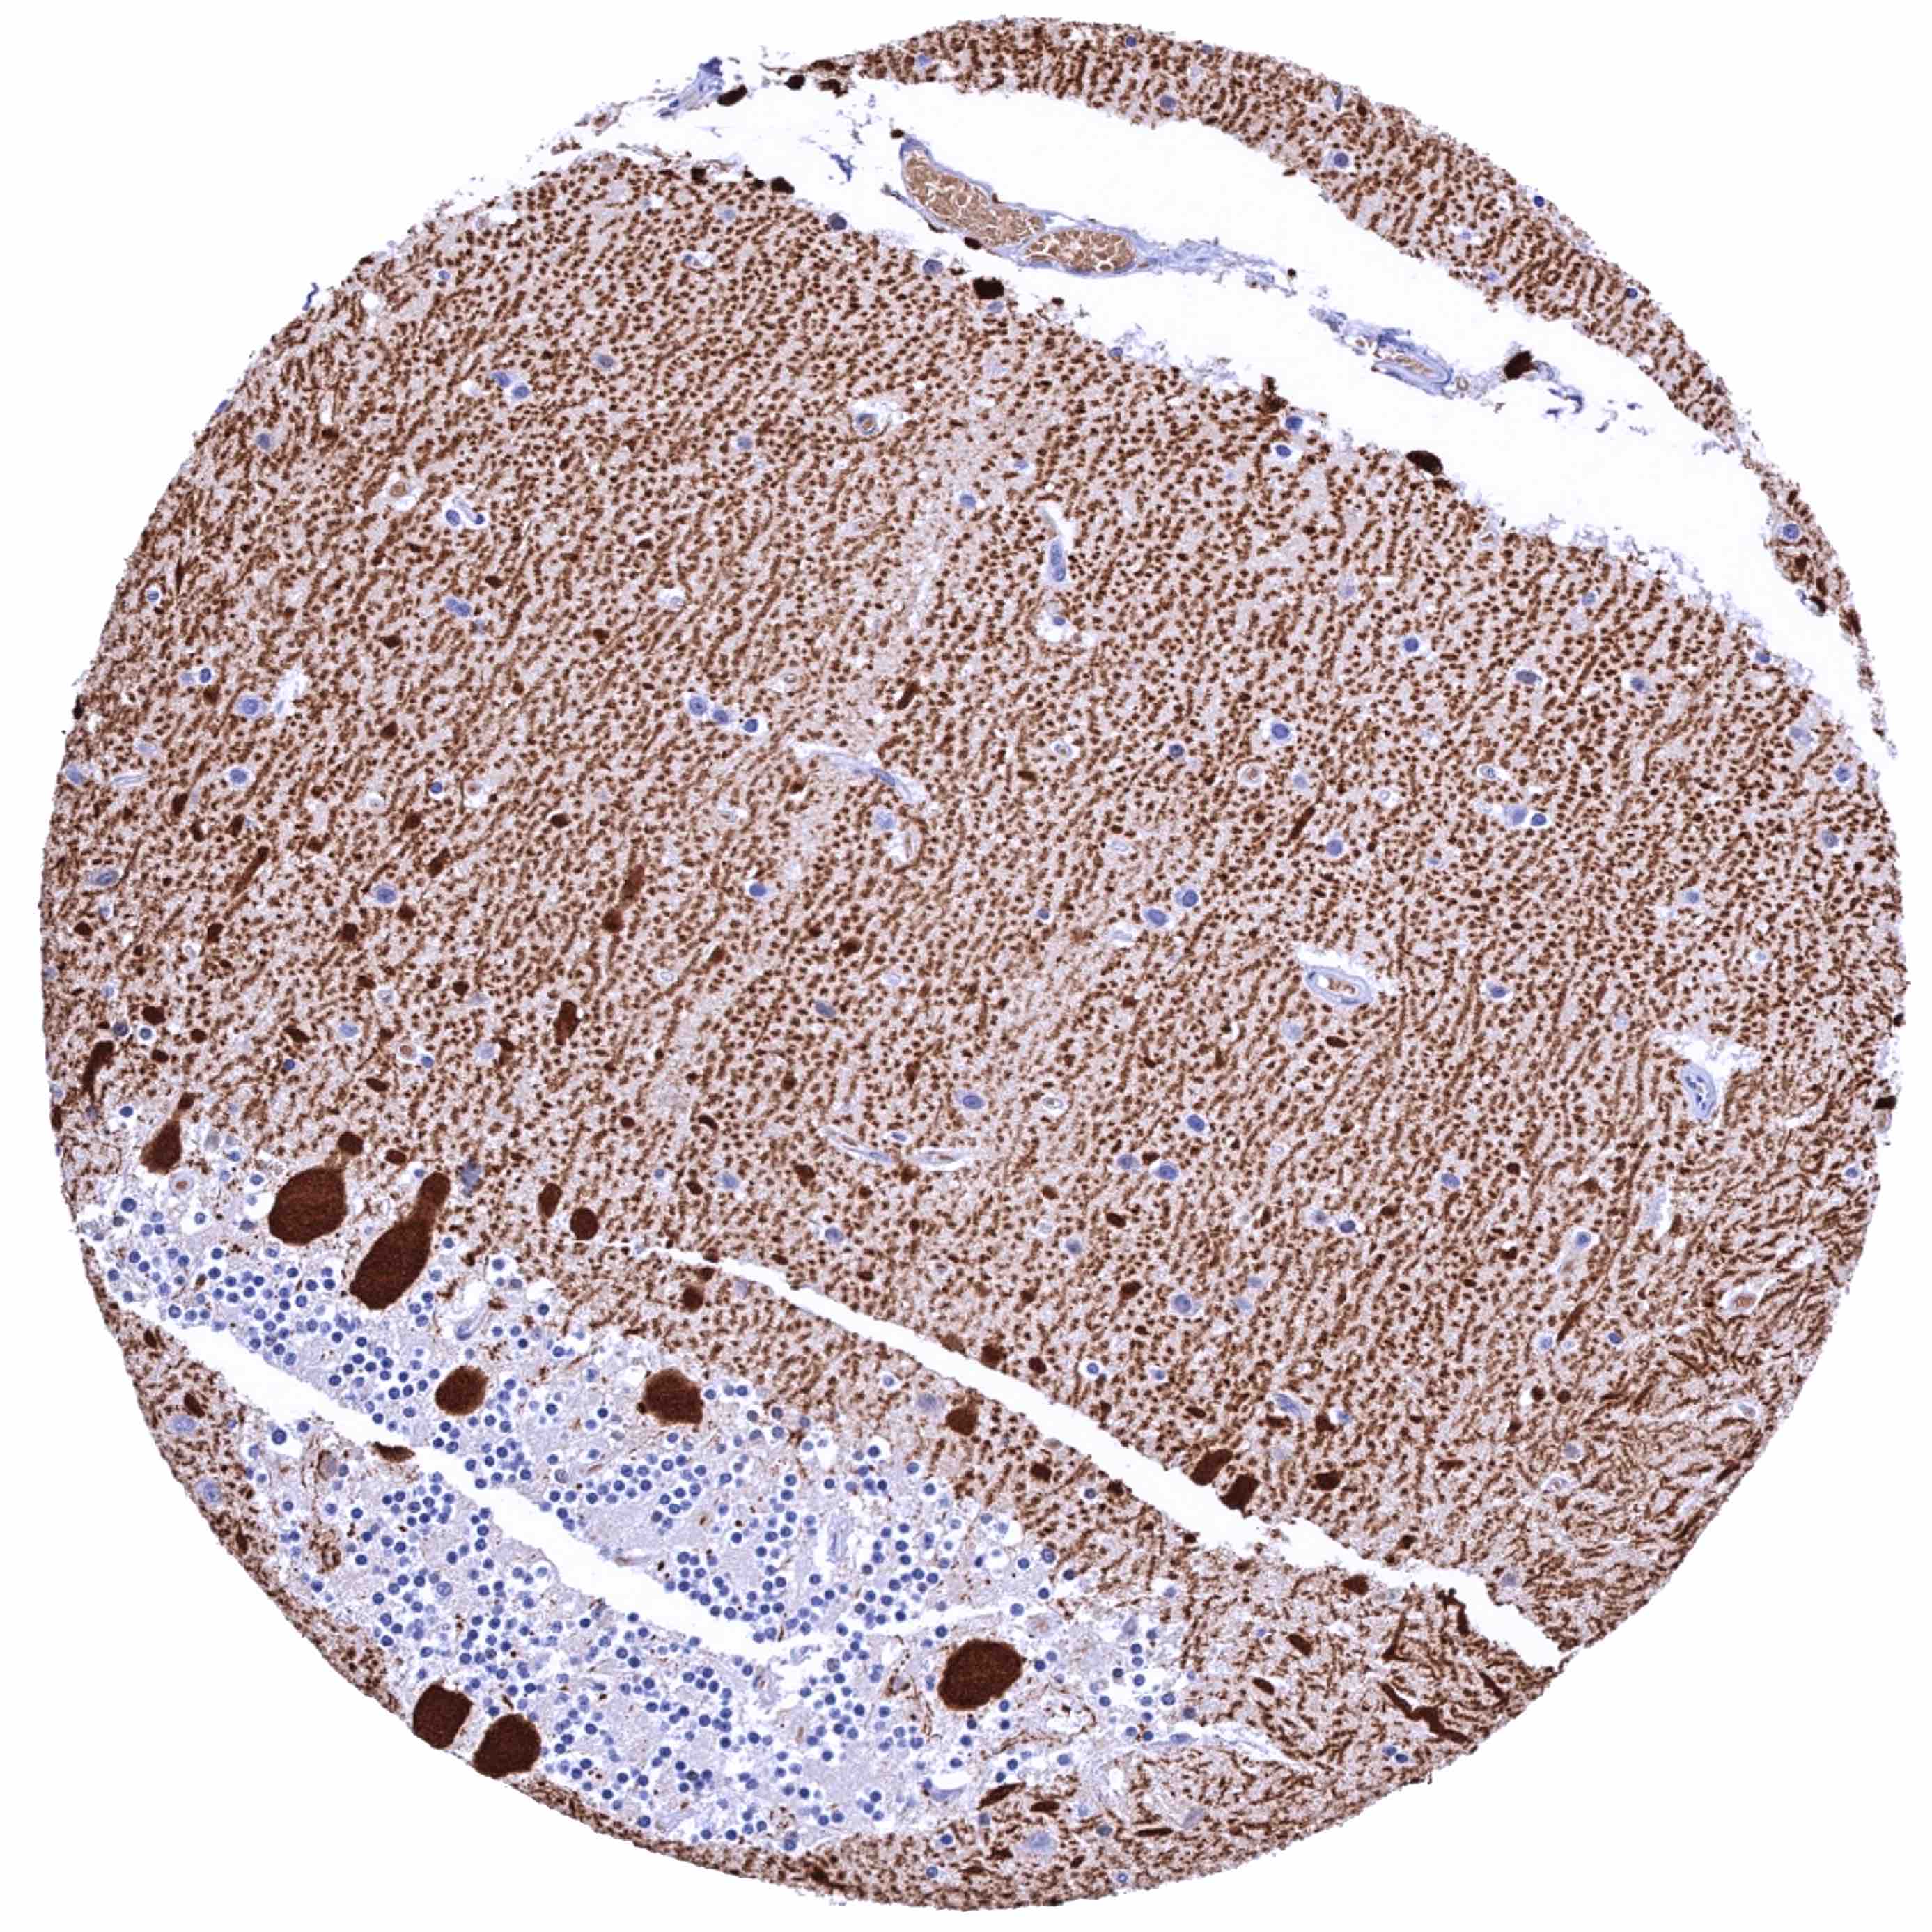

Cerebellum, cortex (molecular layer, Purkinje cell layer, granule cell layer) – Strong Calbindin 1 staining of Purkinje cells and of associated axonal fibres.